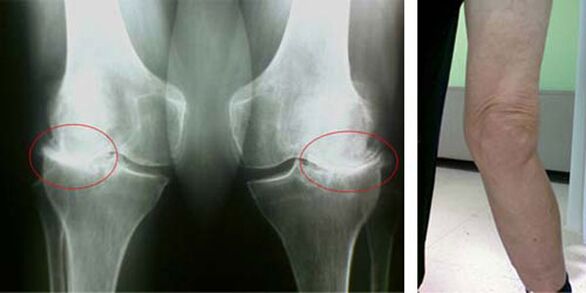

In a healthy knee joint, cartilage is a type of lining that does not allow the bones to touch, thus eliminating the possibility of damage while walking. Affected cartilage cannot cope with this function, so there are signs of stiffness in the joint during movement, accompanied by pain. This condition becomes permanent due to internal pathological changes, when the thinning of cartilage tissue leads to thickening of the bones and creates conditions for the appearance of bone spurs - osteophytes, which cause acute pain.

The initial stages of the appearance of such pathology as osteoarthritis of the knee joint are not visually manifested in any way. However, after some time, the patient notices signs of knee deformity, as well as the characteristic curvature along the axis of the lower leg (directed inwards). There is also a crunch when you need to bend your leg.

The presence of pain, limited movement in the knee forces the person to consult a doctor and undergo an examination. To do this, he must pass tests and make an X-ray of the diseased joint. If these measures are not sufficient to confirm osteoarthritis of the knee joint, then magnetic resonance imaging is performed. Based on the collected data, the doctor chooses the best treatment methods.